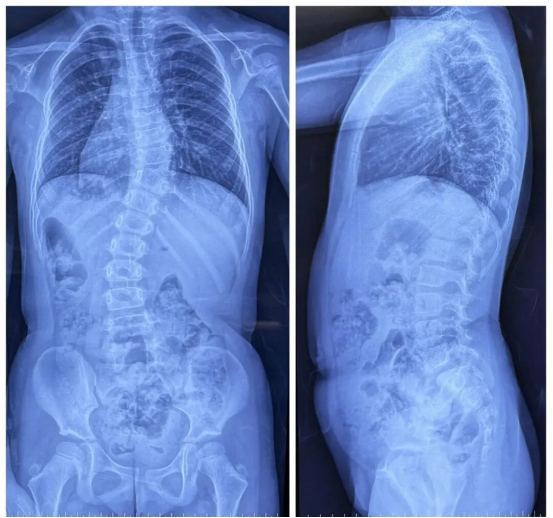

Patient: Female, 5 years old

Clinical Symptoms: Asymmetrical back, uneven shoulders, scoliosis

Surgical Indication: Congenital hemivertebra deformity accompanied by scoliosis, which affects normal growth and development. Surgical correction was necessary. Early surgical intervention can effectively prevent deformity progression and improve prognosis.

Surgical Approach: Posterior hemivertebrectomy combined with short-segment fixation and fusion

Surgical Goals: Eliminate the deforming element, correct spinal deformity, restore spinal balance, and preserve the patient's growth potential.